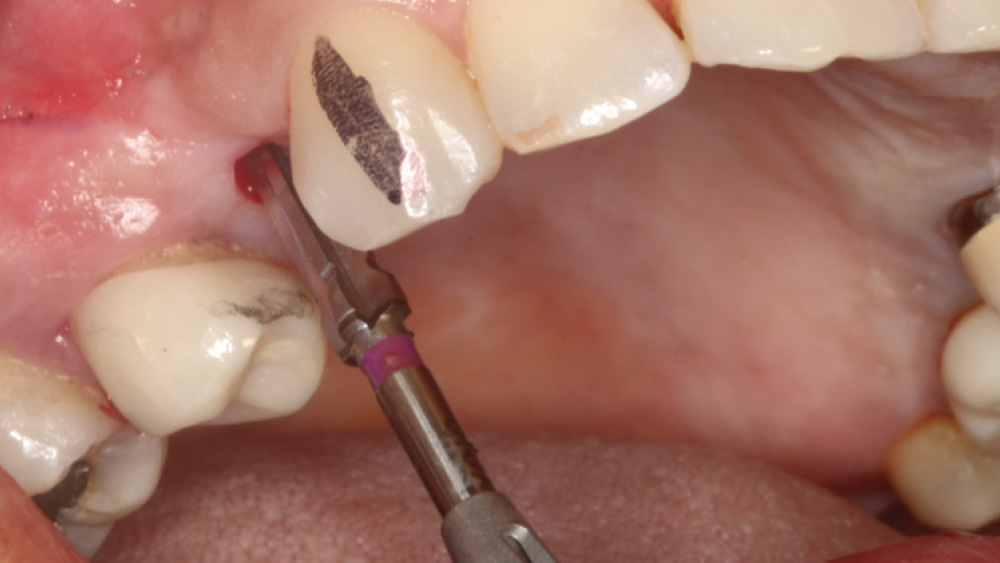

When the attached tissue is minimal, a flap procedure allows the surgeon to reposition the flap to create more attached gingiva and improve the interdental papillae at the implant site. Reflecting a gingival flap also enables the practitioner to more clearly see the final position of the implant at the crest of the bone. If it’s necessary to visualize the bone during the surgical procedure due to uncertain ridge width or height, flap reflection is the safest, most predictable approach.

The following case, which I performed alongside Dr. Stephanie Tilley of Pensacola, Florida, illustrates the use of both surgical techniques for the same patient, who presented with edentulous spaces in the areas of both right and left maxillary first bicuspids. Due to varying soft-tissue volume on each side of the arch, implant surgery was performed using a flapless procedure for one site, while the attached gingiva was reflected to expose the available hard tissue for the other. As a result of proper site evaluation, treatment planning and restorative-driven implant placement, both surgical techniques led to successful outcomes for the patient.